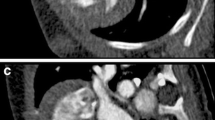

Figure 3 and 4 illustrate representative images for FBP, FBP50 %, and AIDR50 % reconstructions from the same subject. Image noise increased when reconstructing with FBP after a simulated 50 % dose reduction. The AIDR3D reconstruction 50 % dose reduction achieved smoothness of the structural border.

Representative axial (a–c) and corresponding curved multiplanar reformatted images (d–f) of the right coronary artery with coronary artery disease (arrow) from three reconstruction methods performed on one subject (window width/level = 1,200/200). a and d were reconstructed using conventional filtered back projection (FBP); image noise increases in b and e that were reconstructed with FBP after a simulated 50 % dose reduction (FBP50 %). c and f were reconstructed with AIDR3D applied to the raw data after the application of the 50 % simulated noise reduction (AIDR50 %)